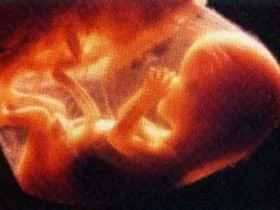

Ученые утверждают, что влияние КТ на плод до сих пор досконально не изучено. Но именно беременные женщины наиболее подвержены радиоактивному облучению.

За одну процедуру КТ зародыш получает облучение на уровне 4,3 миллигрей, примерно 2,91 миллигрей при флюороскопии, 0,40 миллигрей при радионуклидной диагностике и 0,43 миллигрей во время рентгена.